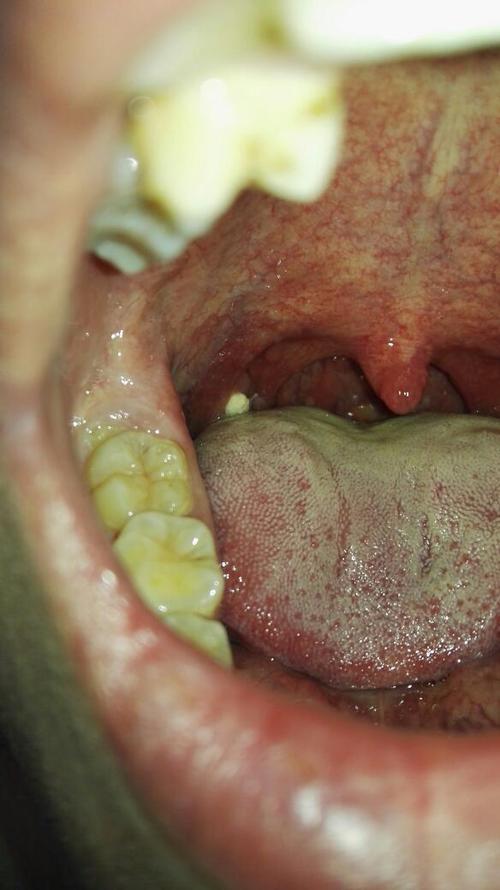

b. 念珠菌病(鹅口疮 / 雪口病)

- 位置: 舌头、颊内侧、上颚、口角。

- 外观描述: 表面为乳白色、豆腐渣样或凝乳状的斑片,略微凸起,斑片不易被擦掉,如果强行刮除,下方会露出红色的、容易出血的糜烂面。

- 感觉: 可能伴有口干、烧灼感或味觉改变,常见于婴幼儿、老年人、免疫力低下者或长期使用抗生素者。

- 文字图解:

想象一下,舌头上长了一层厚厚的、像牛奶干掉或豆腐渣一样的白色物质,擦不掉,一擦就疼、就出血,这是真菌感染,需要抗真菌药物治疗。

(这是鹅口疮的示意图,白色斑块不易擦除)